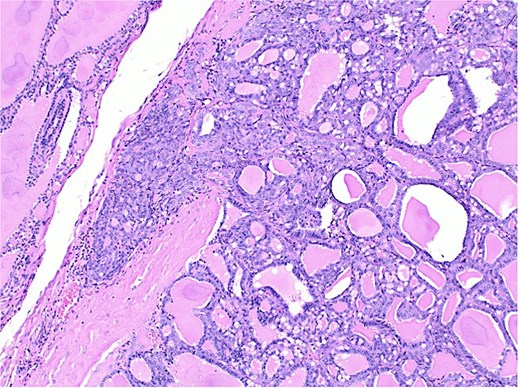

Histological section showing follicular carcinoma in the upper region and papillary carcinoma in the lower region, with intervening non-neoplastic thyroid tissue.

The final pathological report revealed a 1.4 cm classic papillary carcinoma in the isthmus, with extrathyroidal extension, without vascular, lymphatic, or perineural invasion, and with clear margins. In the left lobe, a minimally invasive follicular carcinoma of 3.5 cm was diagnosed, with capsular and limited vascular invasion (less than four vessels), without lymphatic or perineural invasion, and with clear margins (Figs 2–4).